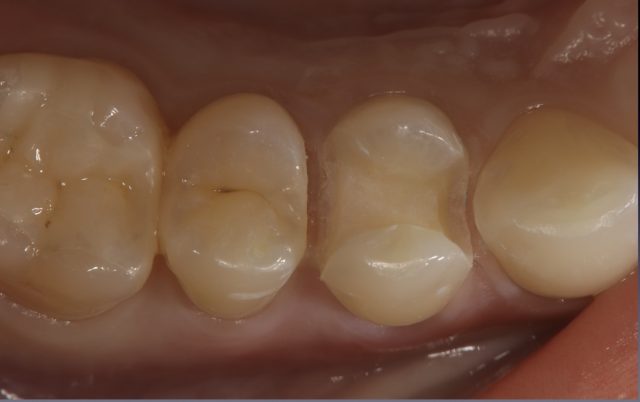

セラミックインレーの審美補綴治療

Before

After

| 診断名 | セラミックインレーの審美補綴治療 |

| 年齢・性別 | 20代・女性 |

| 治療期間・回数 | 2週間~3週間/2回 |

| 治療方法 | セラミックインレーによる審美補綴治療 |

| 費用 | 55,000円(税込み) |

| デメリット・注意点 | 保険が適用できないため自費診療になる。 セラミックスインレー・クラウンに強い力がかかると割れてしまう恐れがあるため、歯ぎしりや食いしばりが癖になっている患者様にはおすすめできない場合がある。 |